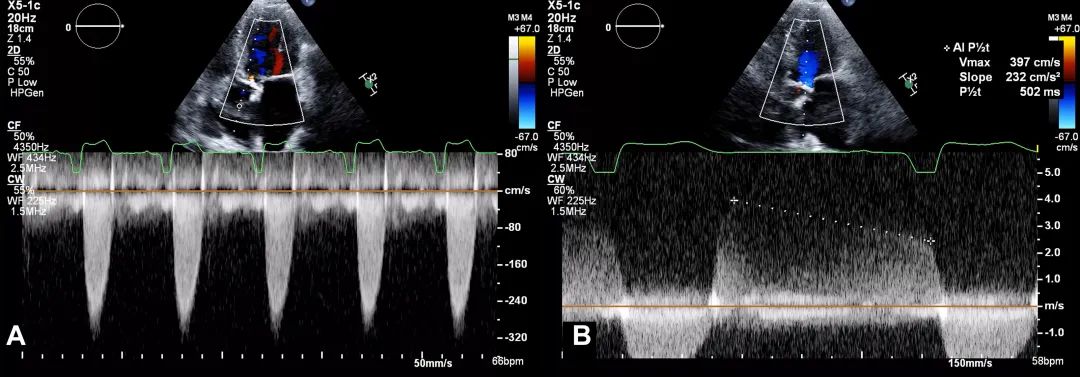

8、心尖五腔心切面:将连续多普勒(continuous-wave Doppler,CW)取样线对准主动脉瓣血流方向,测量主动脉瓣峰值流速和跨瓣压差,并评估是否存在主动脉瓣反流。测量主动脉瓣峰值流速波形(图9)。

图9. 心尖五腔心切面连续多普勒评估

心尖五腔心切面:将连续多普勒取样线对准主动脉瓣血流方向,测量主动脉瓣峰值流速(A)和跨瓣压差,并评估主动脉瓣反流(B)。

11、心尖三腔心切面: 将连续多普勒取样线对准主动脉瓣血流方向,获得主动脉瓣峰值流速、跨瓣压差,并评估主动脉瓣反流(AR)(图12)。测量此切面下主动脉瓣峰值流速波形。

图12. 心尖三腔心切面连续多普勒评估

心尖三腔心切面:将连续多普勒取样线对准主动脉瓣血流方向,获得主动脉瓣峰值流速、跨瓣压差,并评估主动脉瓣反流。